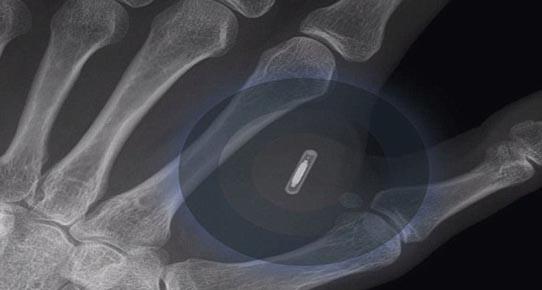

Avustralya’nın Brisbane kentinde yaşayan Ben Slater, eline taktırdığı mikroçip sayesinde elinin bir hareketiyle kapıları ve ışıkları açıp kapatmayı başardı. Slater, bir dövmecide eline yerleştirilen pirinç tanesi büyüklüğündeki mikroçip sayesinde, yeni iPhone 6 ile de ‘ iletişim kurmayı’ hedefliyor.

Tüm dünyada merakla beklenen iPhone 6, Apple tarafından yarın piyasaya sürülecek. Reklam direktörü Slater, Daily Mail Avustralya’ya, geleceğin teknolojilerinin daima ilgisini çektiğini söyledi. Slater, Apple’ın yeni akıllı telefonunun elinde yerleştirdiği çipi de okuyabileceğini düşünüyor. İnsana mikroçip uygulaması Avustralya için yeni olsa da ABD’de 2004 yılından beri hızla yaygınlaşıyor. Mikroçiplerde kronik hastalığı olan kişilerin sağlık bilgileri tutuluyor.